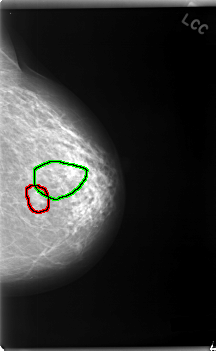

C_0038_1.LEFT_MLO

FILE: C_0038_1.LEFT_MLO.OVERLAY

TOTAL_ABNORMALITIES 2

ABNORMALITY 1

LESION_TYPE MASS SHAPE OVAL MARGINS CIRCUMSCRIBED

ASSESSMENT 4

SUBTLETY 5

PATHOLOGY BENIGN

TOTAL_OUTLINES 1

BOUNDARY

ABNORMALITY 2

LESION_TYPE CALCIFICATION TYPE FINE_LINEAR_BRANCHING DISTRIBUTION CLUSTERED

ASSESSMENT 5

SUBTLETY 4

PATHOLOGY MALIGNANT